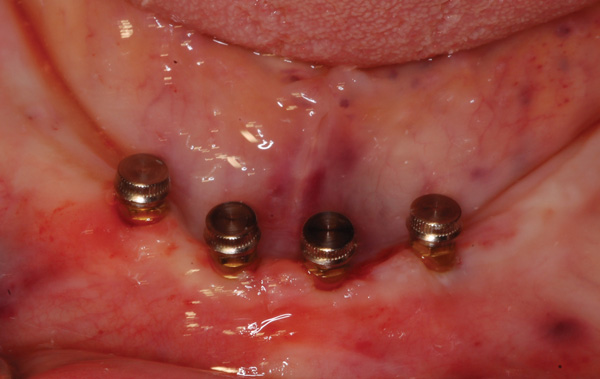

Mini implants serve a purpose and are ideally suited with regard to removable prosthetics when the patient’s complaint is “lift-off” of the denture. Implants with “O” ring (ball) heads and attachments can provide sufficient retention to prevent the denture from lifting off the ridge during function when the patient is speaking, chewing, and using generalized tongue movements. When the patient presents with a non-implant–retained denture and the denture has significant lateral displacement, the mini implants will be loaded laterally under function. As discussed, implants manage lateral loading the worst, which leads to bone loss, mobility, or a combination of these two occurrences. The narrower the implant diameter, the less bone-to-implant contact is present (less surface area), and the less lateral loading the implant can tolerate under normal function before issues arise. Considerations for use of mini implants relates to the available ridge to provide lateral bracing as well as distribution of the implants around the arch. Due to less bone-to-implant contact, it has been recommended that when using mini implants, a minimum of 4 be placed around the arch, which is typically adequate in the mandibular arch (Figure 13). Due to lower bone quality (density) in the maxillary arch, placement of more than 4 mini implants may be a wise routine recommendation. In addition, the implants should be spaced with sufficient distance between the fixtures to distribute the retention over as much area as is available. Placing mini implants close together does not necessarily increase retention, and it thins the acrylic in the denture between the mini implant attachments within the denture, which can lead to stress fractures of the denture base.

Fig 13. Mini implants with attachments in the mandible with minimal vestibular depth but adequate depth of the floor of the mouth.

Figure 13